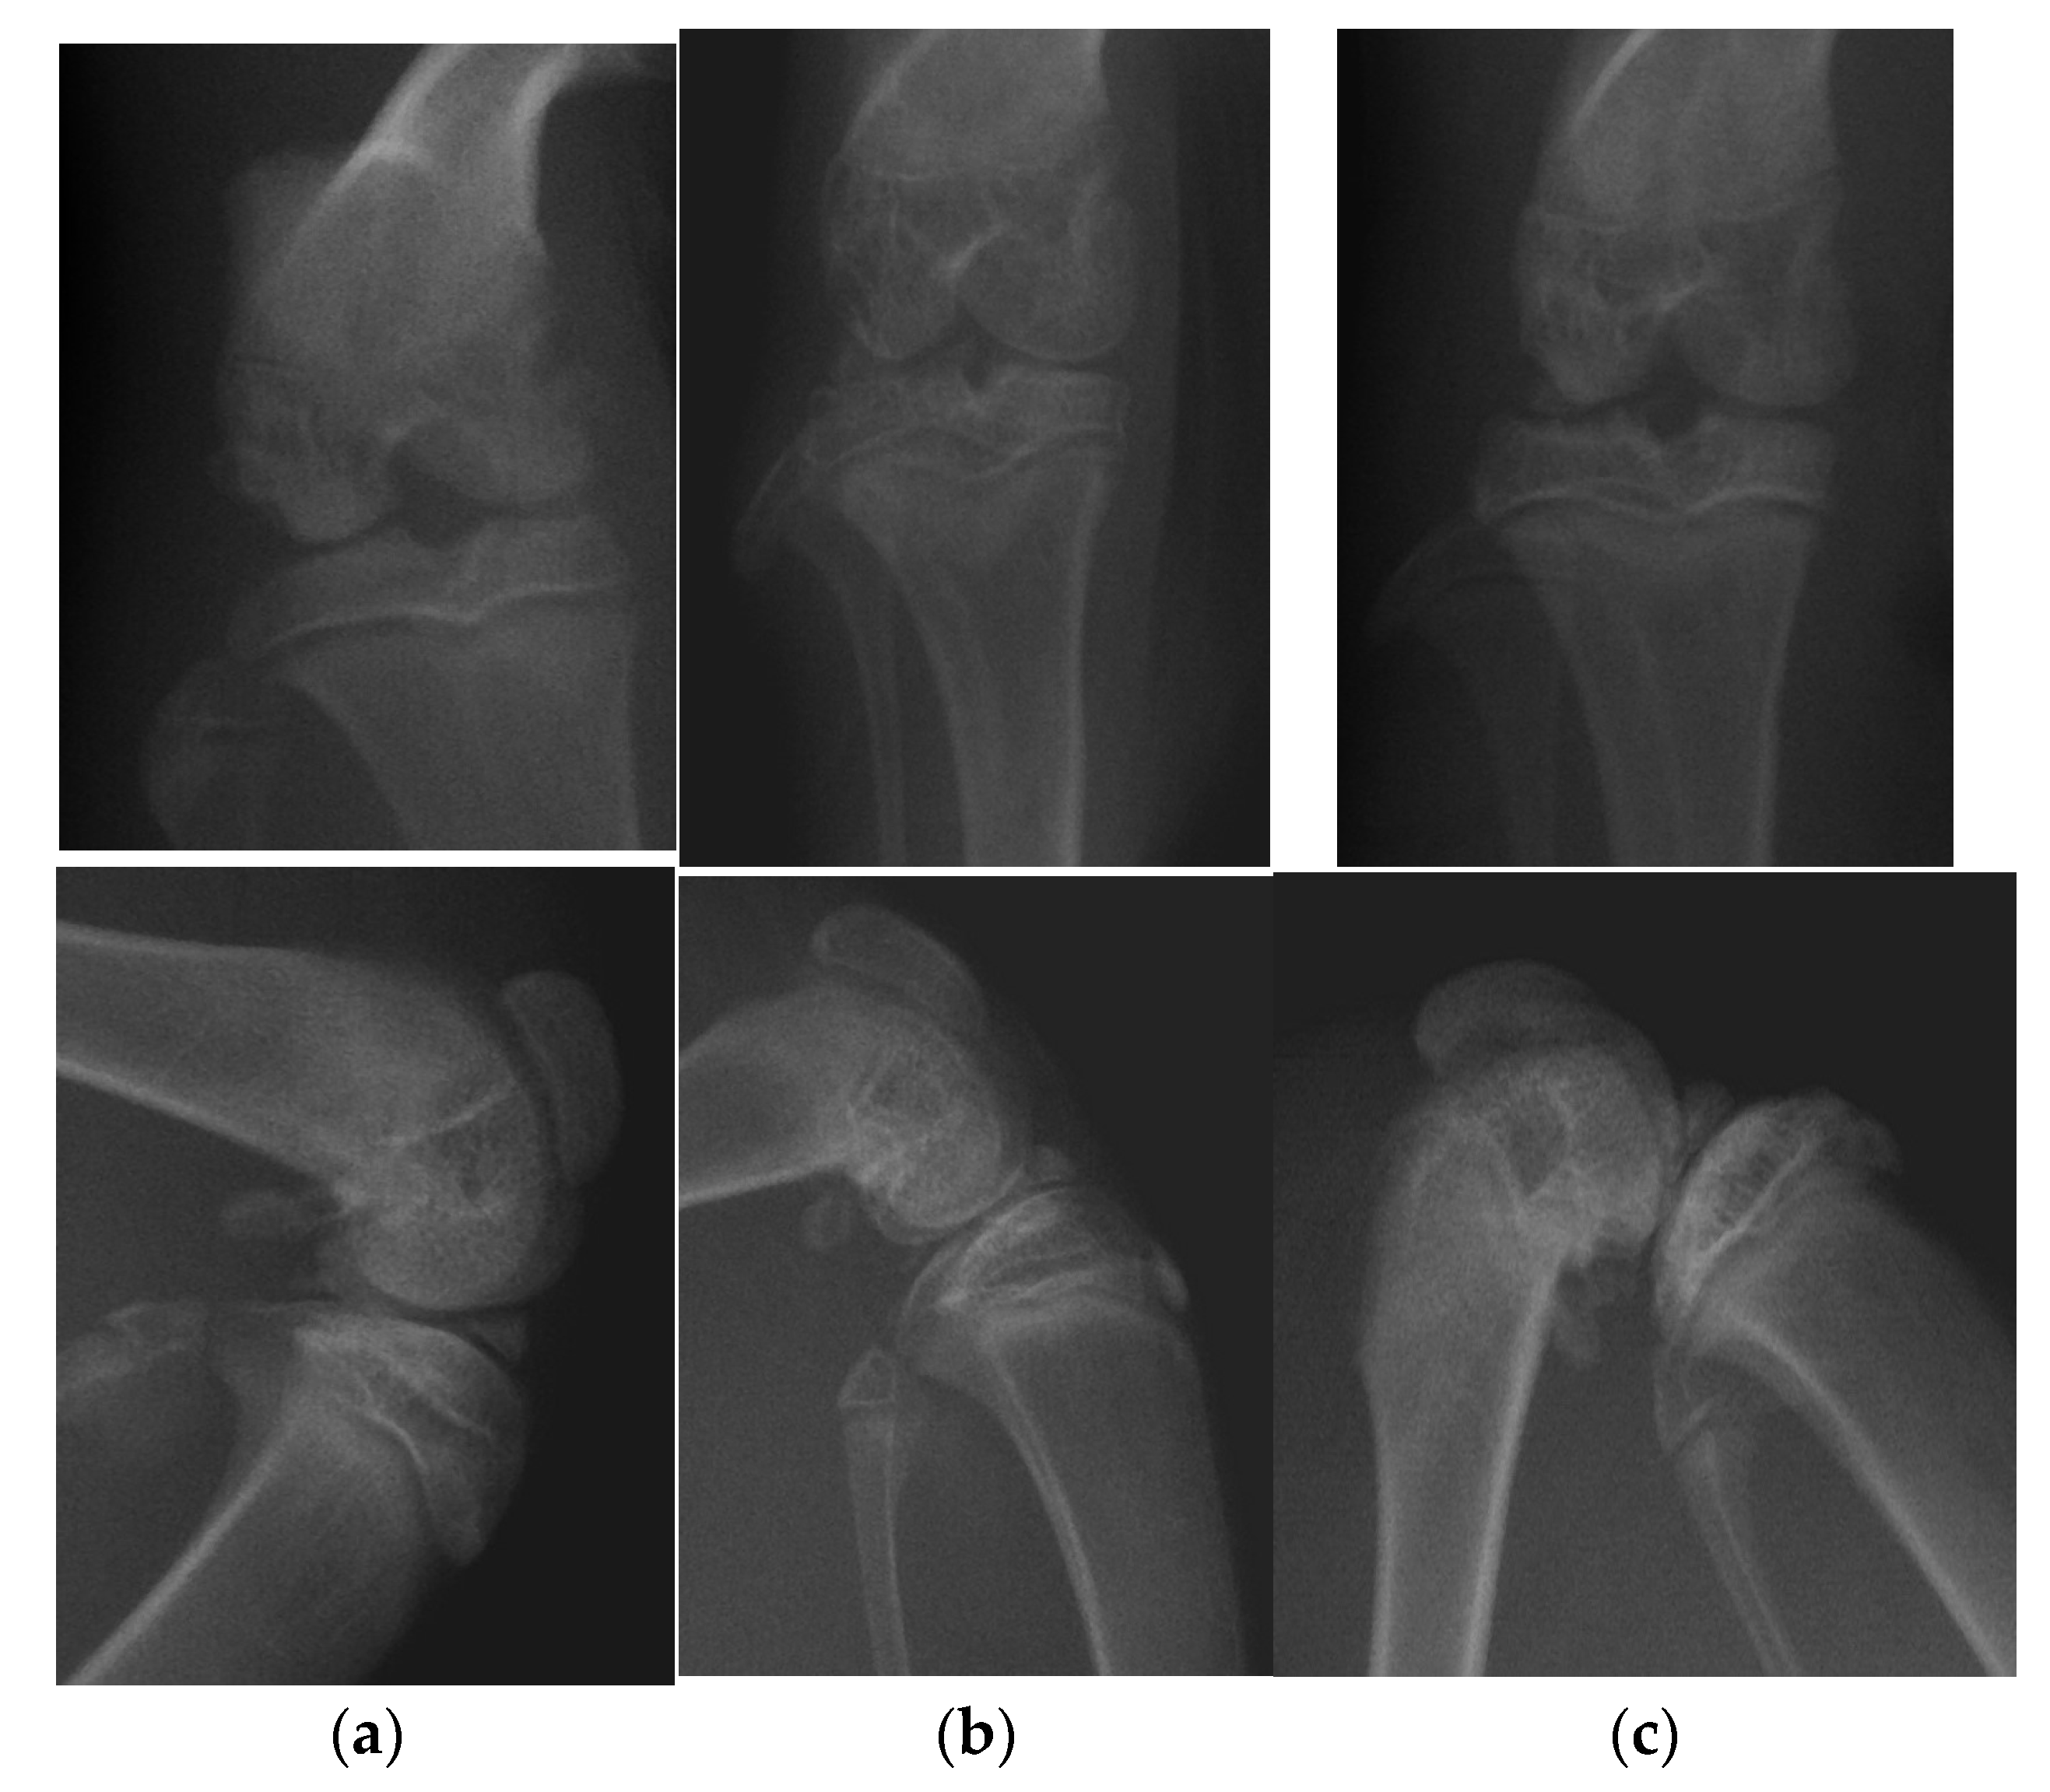

2.1. Radiological Examination

| Grade | Severity of OA |

|---|---|

| Grade 0 | definite absence of X-ray changes of osteoarthritis |

| Grade I | doubtful joint space narrowing and possible osteophytic lipping |

| Grade II | definite osteophytes and possible joint space narrowing |

| Grade III | moderate multiple osteophytes, definite narrowing of joint space and some sclerosis and possible deformity of bone ends |

| Grade IV | large osteophytes, marked narrowing of joint space, severe sclerosis and definite deformity of bone ends |